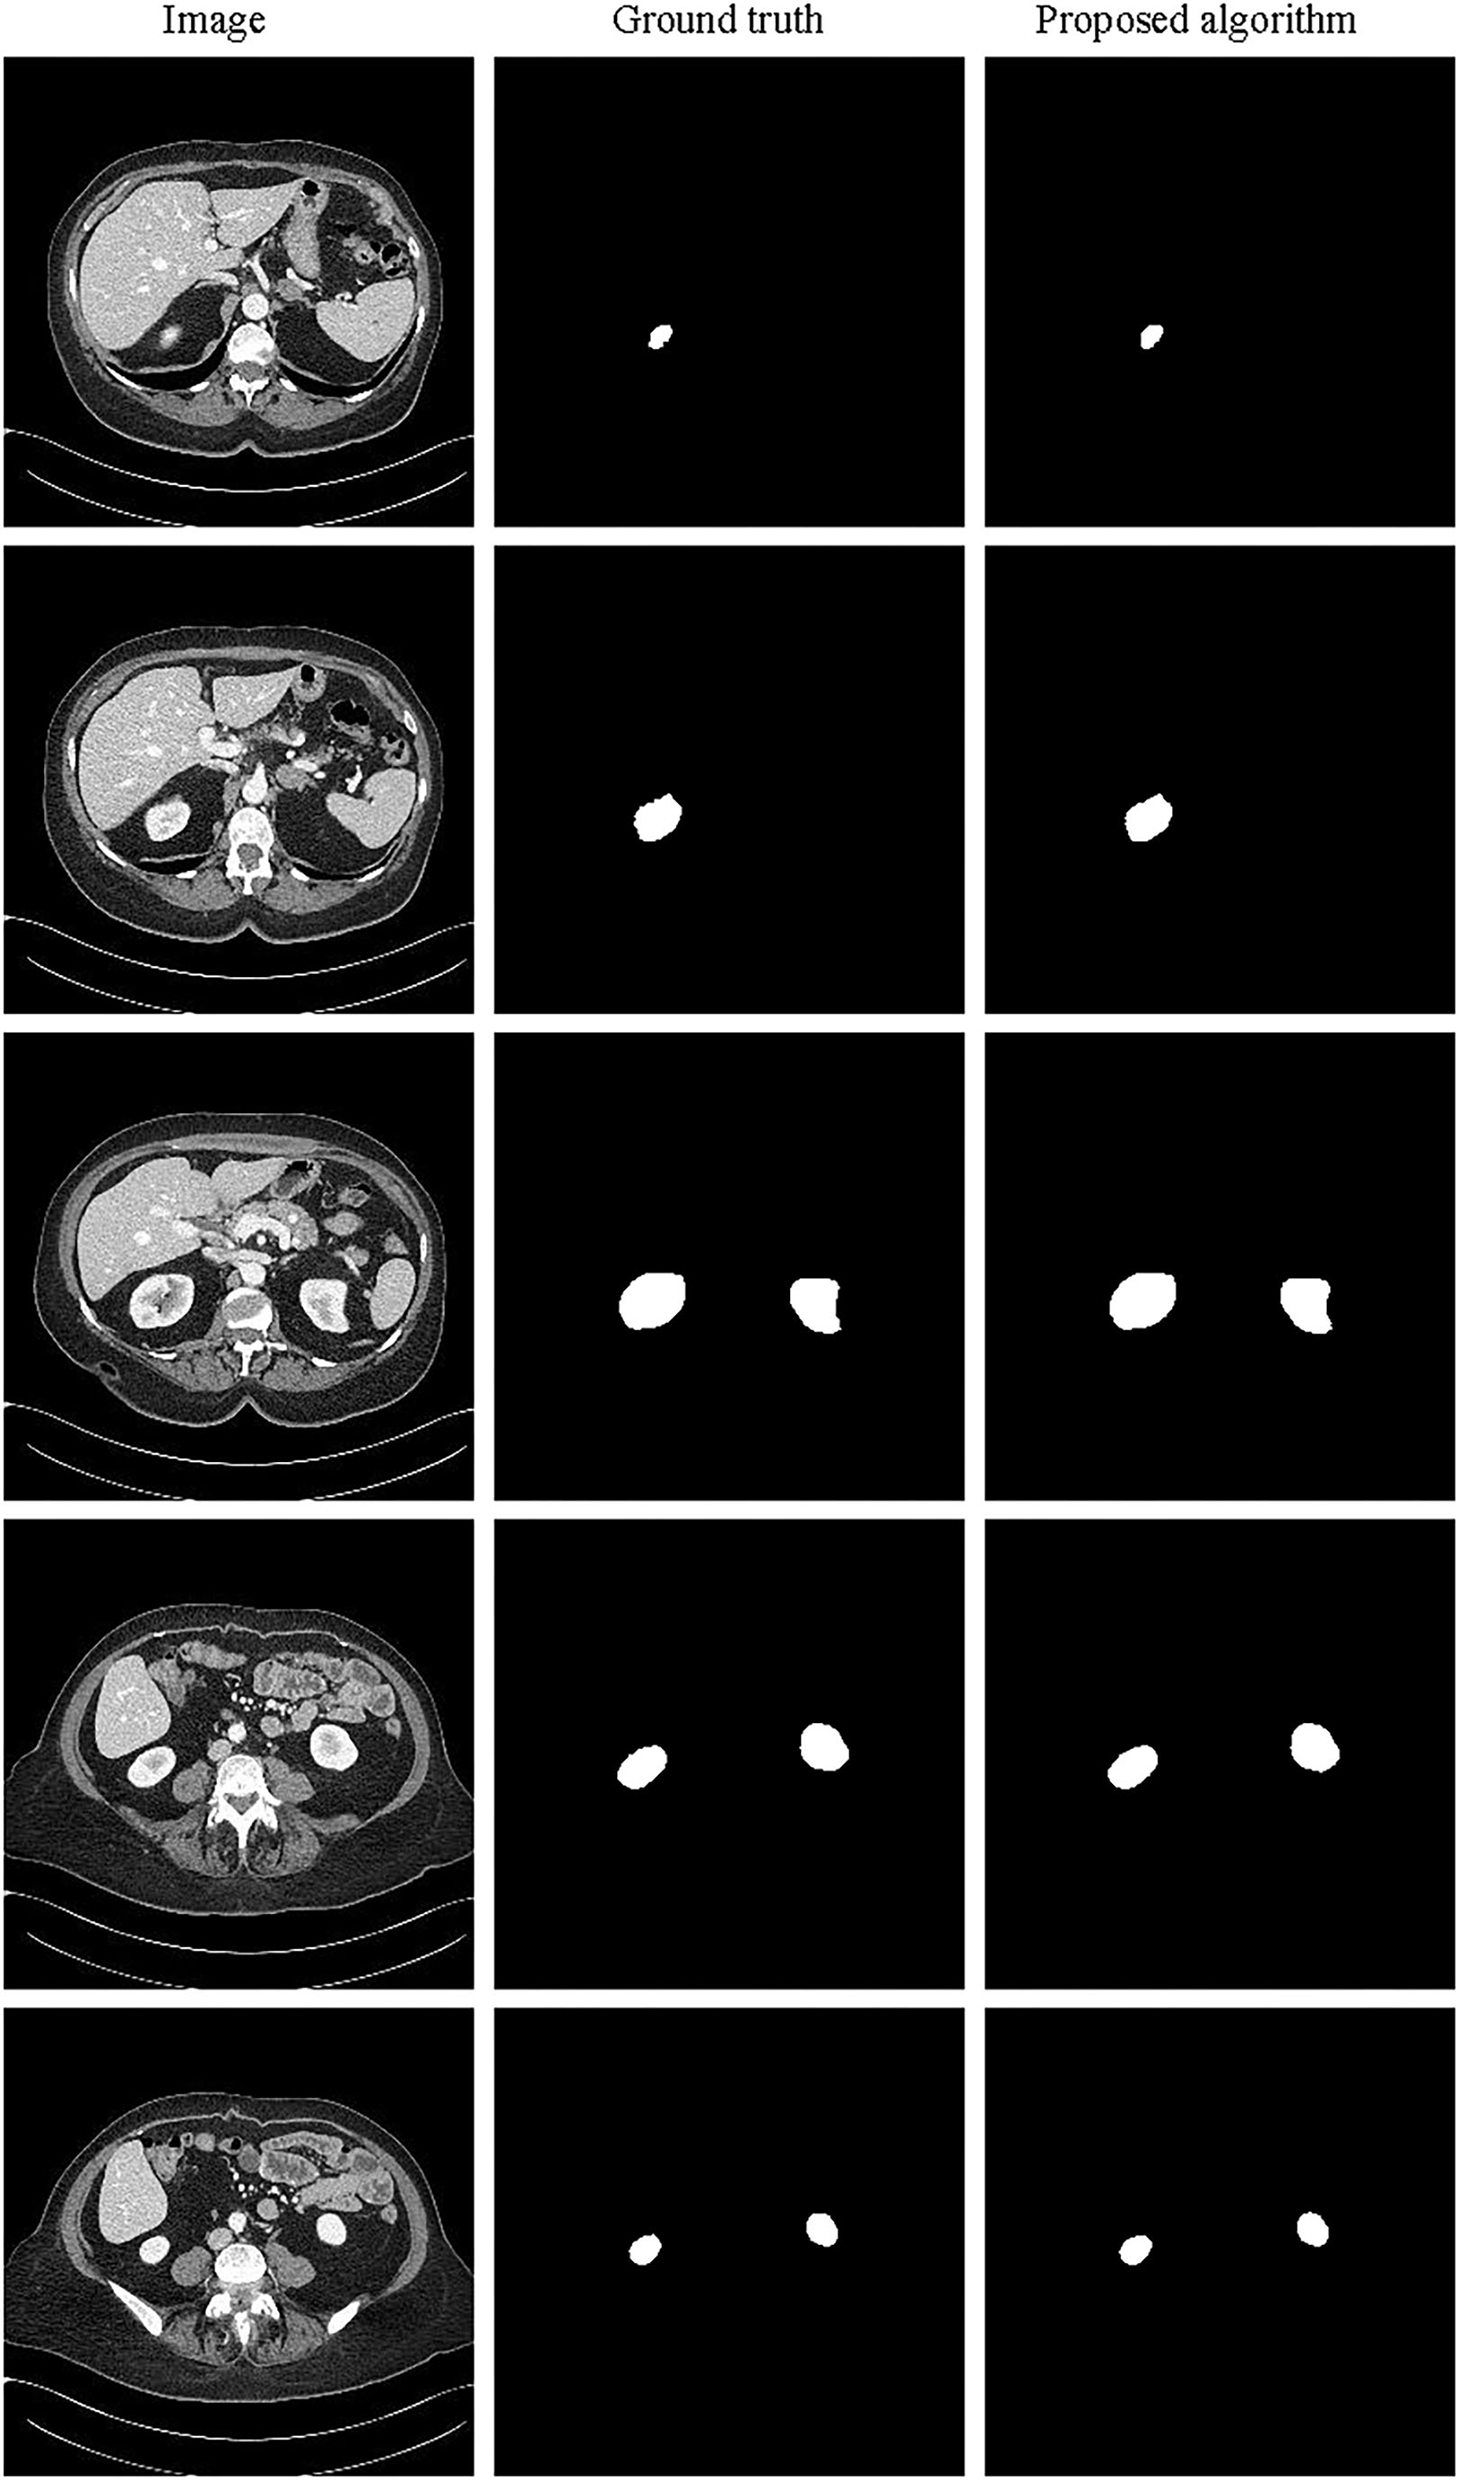

It can be seen from the experimental results that the model still performs well for the 3D segmentation of the kidney. Comparing with the classic 3D U-Net network, the accuracy of kidney segmentation is significantly improved on the verification set. Furthermore, the segmentation ability of the model is still strong on the test set, even exceeding the performance of the verification set.

The partial segmentation result is selected from the test set as shown in Figure 11. The left column is the original image, the middle column is the annotated kidney image, and the right column is the segmentation result. It can be found that the 3D segmentation results of the kidney are also very close to the real labels. Since it is only to verify the generalization of the image generation method based on feature restoration, it has not been further analyzed. In the future, we will further study and verify the general 3D image generation method.

Figure 11

Schematic representation of the kidney 3D segmentation results.